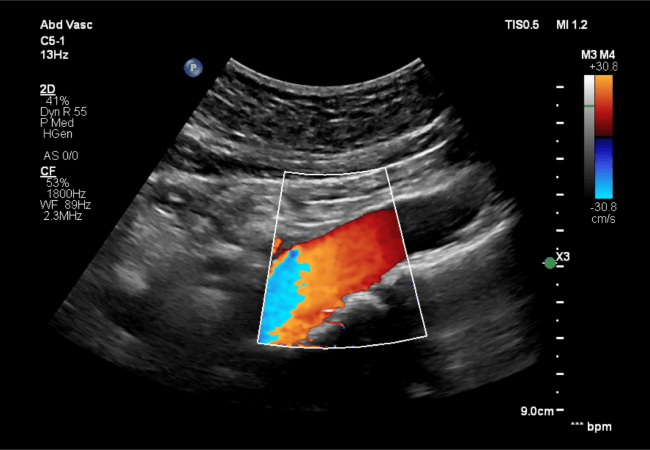

Abdominal Aorta Ultrasound

This test screens for aneurysms in the abdominal aorta, critical for early detection and management of this potentially life-threatening condition.